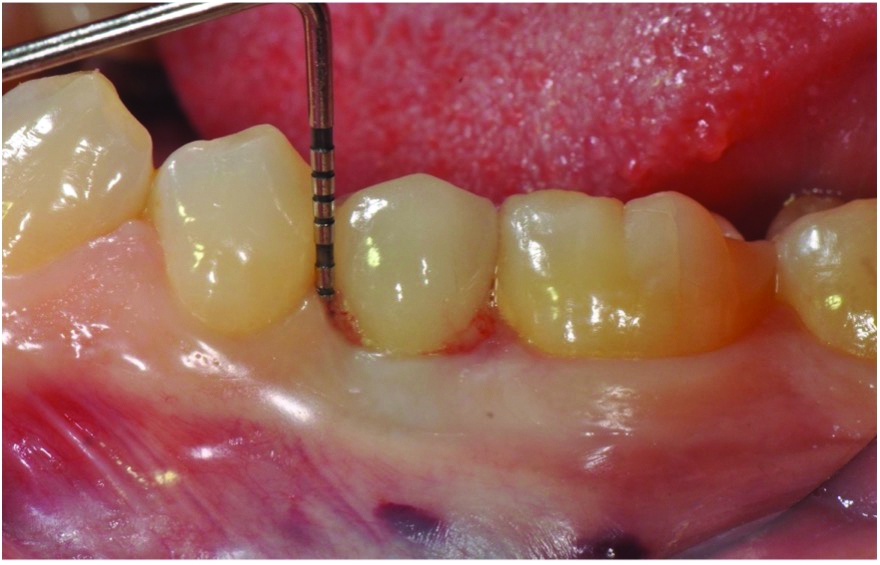

At 5 years post-implant placement, implant site No. 20 showed circumferential depths of 6 mm to 8 mm with heavy bleeding on probing (Figure 1).1,47 The keratinized mucosa width locally recorded 4 mm buccally and lingually, with a thick gingival phenotype. The four-wall intrabony lesion was diagnosed as a class 1c (circumferential) intrabony peri-implant defect with less than 40% defect angulation in the mesial and distal radiographic aspects (Figure 2).48 Additionally, resin cement-associated peri-implantitis was diagnosed.49 The patient preferred to maintain the existing well-fitting crown due to financial concerns. The patient would be considered low-medium risk according to the PIDRA (Table 3). (To view Table 3, the PIDRA for this case, visit compendiumce.com/go/2505.)

Fig 1. The patient presented with a probing depth of 6 mm to 8 mm at site No. 20 and bleeding on probing.

Figure 1